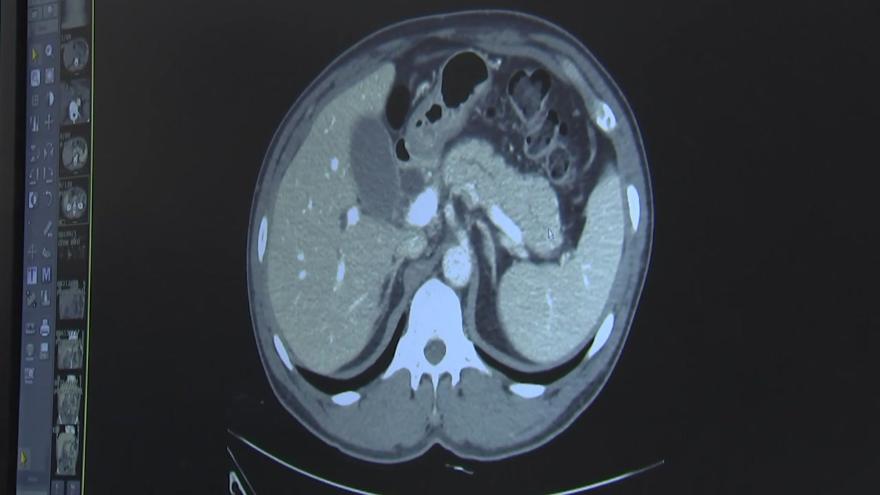

이번 포스팅에서는 췌장암에 좋은 음식과 췌장암에 나쁜 음식들에 대해서 알려드릴테니 꼭 알아두시기 바랍니다. 췌장은 소화 효소를 분비하는 중요한 기관으로 내분비 기능과 외분비 기능을 모두 담당합니다.

내분비 기능은 인슐린과 글루카곤 호르몬을 분비하여 혈당을 조절하는 것이고, 외분비 기능은 지방을 분해하는 효소를 분비하여 소화를 돕는 것입니다. 또한 췌장은 혈당을 담당하는데, 췌장암 환자의 주요 문제 중 하나는 혈당 관리에 문제가 있고 식습관에 주의하지 않으면 당뇨병에 걸리기 쉽다는 것입니다.

췌장암 환자는 소화액을 분비하는 샘인 췌장에 종양이 생겨 췌장에 문제가 생기면 소화에 문제가 생기고, 췌장에 문제가 생기면 과도한 구토, 식욕부진, 체중감소, 탈수 등이 발생해 건강이 나빠지고 치료 결과도 나빠질 수 있습니다. 그러므로 알려드리는 췌장암에 좋은 음식과 췌장암에 나쁜 음식 리스트들을 꼭 참고하시기 바랍니다.